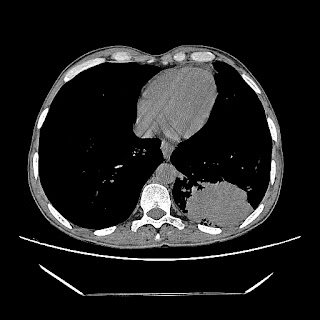

Latest HRCT images: